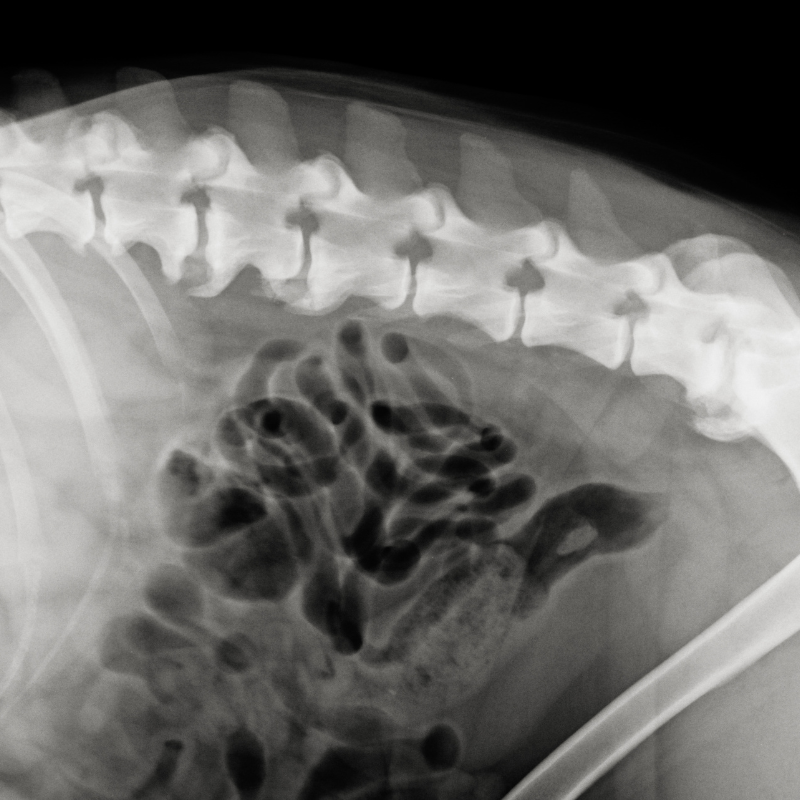

Spondylose

Spondylose ist eine degenerative Erkrankung der Wirbelsäule bei Hunden, die zu Veränderungen des Knochens und des Knorpelgewebes führt. Die Ursachen der Spondylose können...

Bandscheibenvorfall

Die Bandscheiben befinden sich zwischen den Wirbelkörpern der Wirbelsäule und dem Rückenmark. Sie bestehen aus...